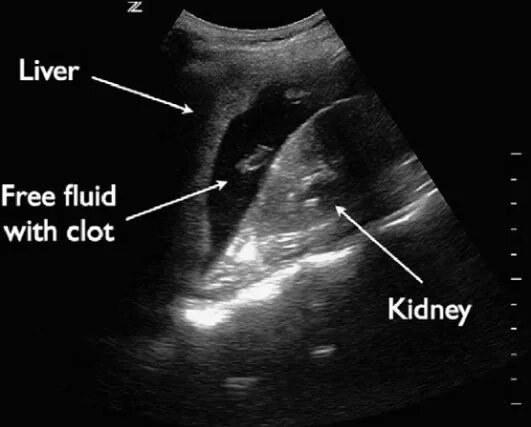

Свободная жидкость в дугласовом пространстве что это